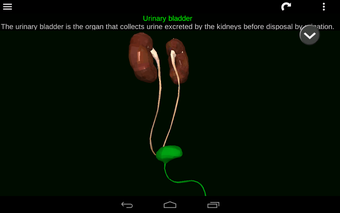

此应用程序显示人体器官的三维模型和所有器官的描述。

您可以触摸每个器官,如心脏、大脑、肺、生殖系统、肝脏、肠道、卵巢、睾丸、胃、肾脏等。

它对所有人都有用,甚至对学生也有用,因为每个解剖器官都以不同的颜色显示。